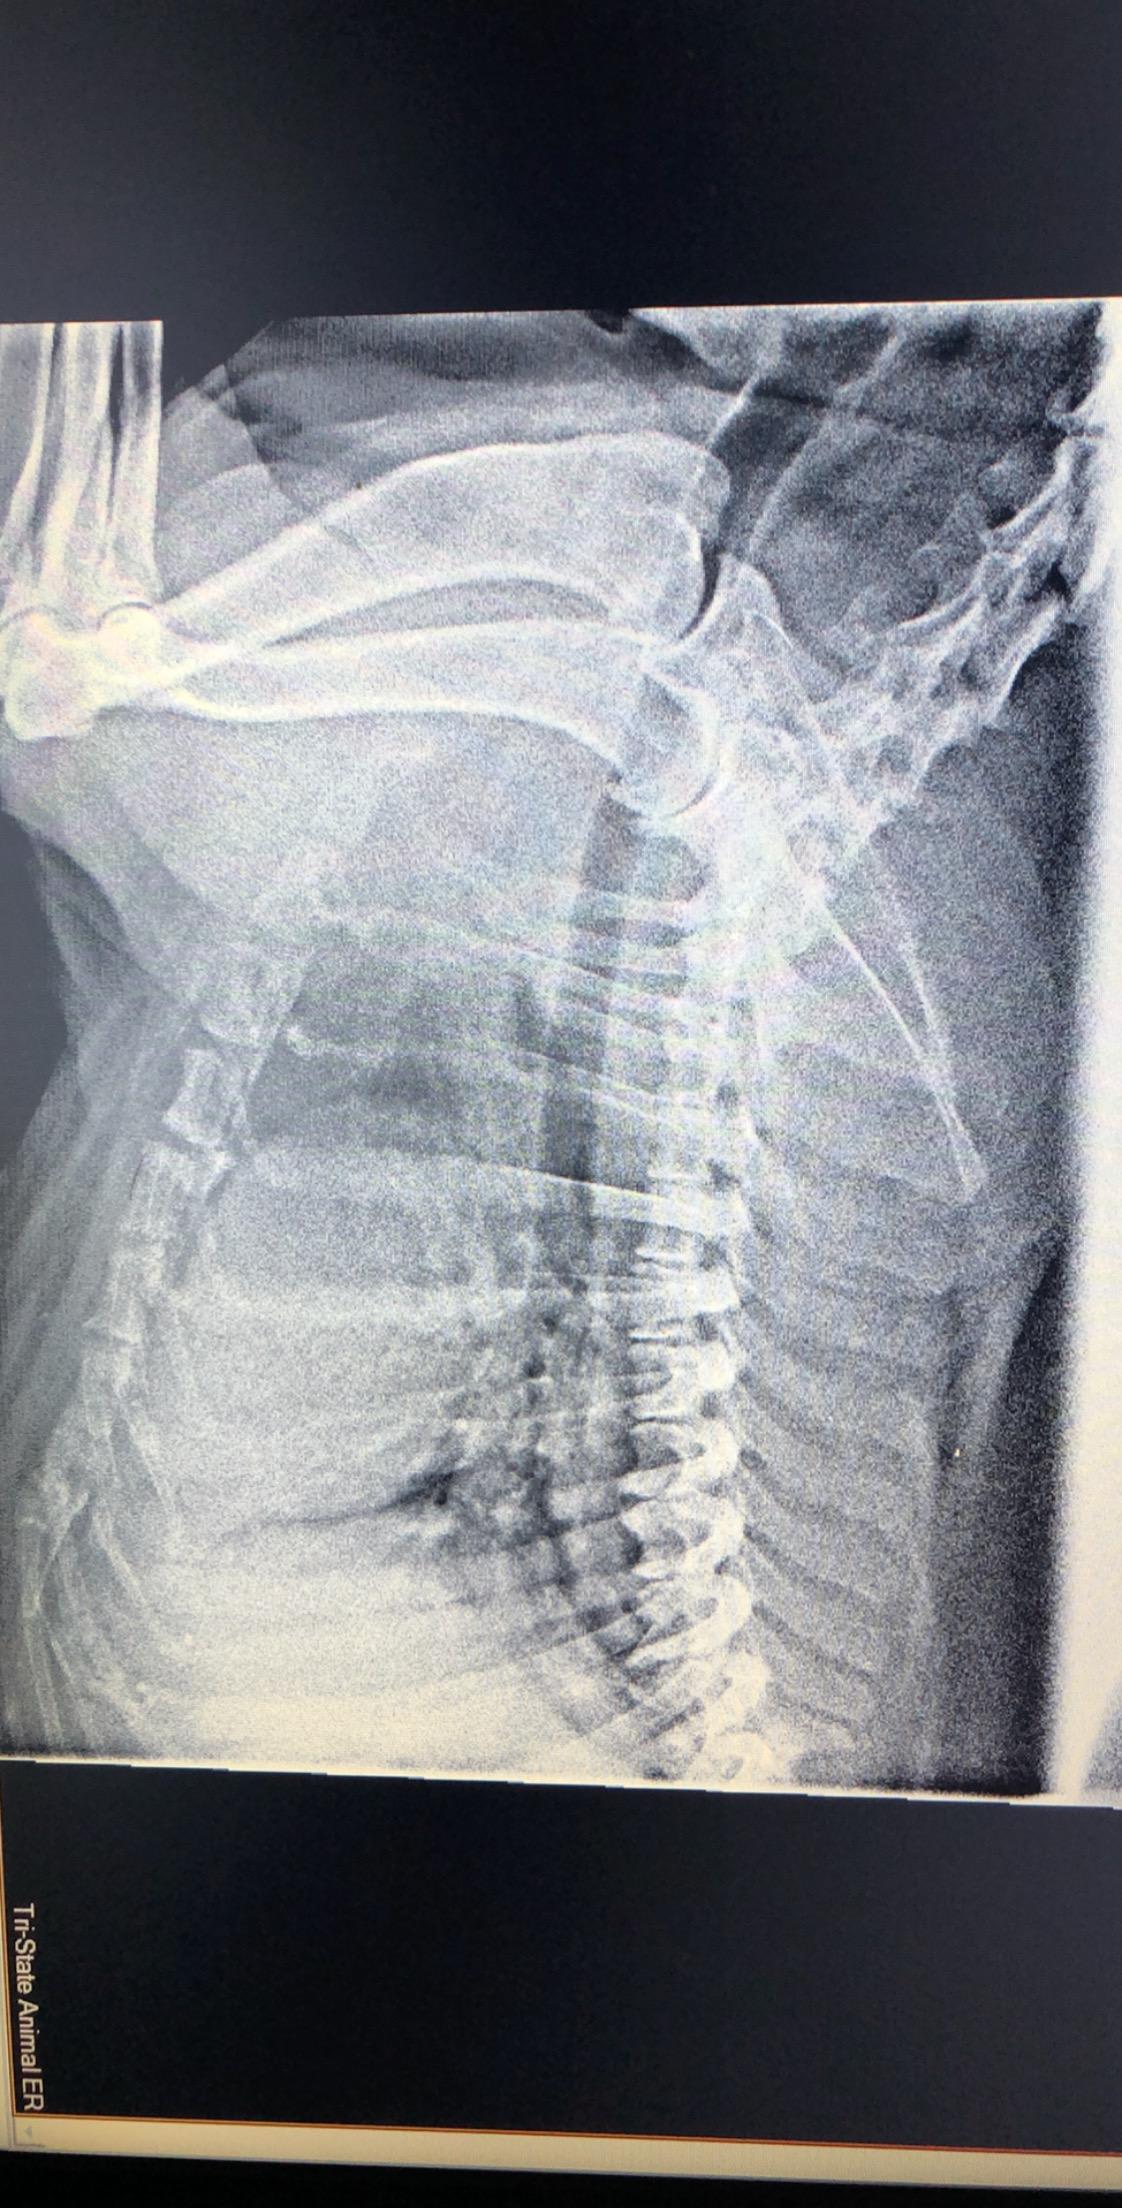

I took my 11 year old lab to the vet last night for coughing and vomiting clear liquid. The tested for pneumonia and Heartworm, both were negative. The vet seemed like he didn’t really know much about what was going on. He said her heart was enlarged and there was something going on with her lungs and maybe the liver, but refused to do any further testing. My question is, what do you think about these X-rays? Do you see anything that could be helpful in finding a diagnosis? Thanks in advance!

Hello and welcome to Petco Pet Education Center, formerly Petcoach. Coughing and bringing up clear liquid could be coughing up stuff instead of vomiting. This is important to try to differentiate. Coughing up liquid is more consistent with heart disease. The x-rays are difficult to read as the image transfer through is of poor quality and to really assess the lungs you need good quality images, however the heart does look a bit enlarged and the lungs do look a bit 'white'. I cannot assess the liver on these radiographs as you cannot see them. An enlarged heart, white lungs (fluid in the lungs), and an enlarged liver is consistent with both right and left sided heart disease. I recommend you return either to your vet, or another vet, and get a specialist ultrasound of the heart (an 'echo') to determine if heart medications are required. Your vet can also listen to the heart to see if a murmur is present in the heart, or 'crackles' are heard on the lungs. Heart disease is very serious and needs medications to manage. Without these Lily unfortunately will essentially drown in her own lungs, if heart disease is the problem. I suggest a recheck as soon as possible to get this figured out. Best of luck with Lily, I hope she feels better soon.